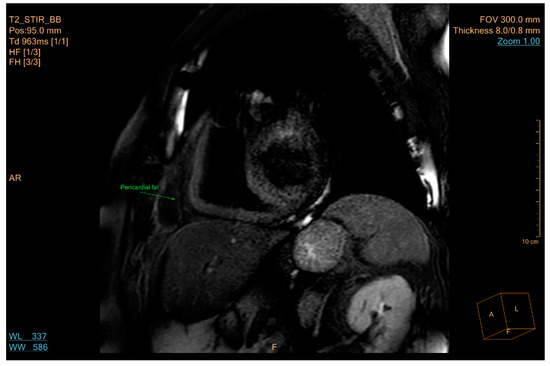

5.3. Imaging

- Samara, A.; Ventura, E.; Alfadda, A.; Goran, M. Use of MRI and CT for fat imaging in children and youth: What have we learned about obesity, fat distribution and metabolic disease risk? Obes. Rev. 2012, 13, 723–732. [Google Scholar] [CrossRef]